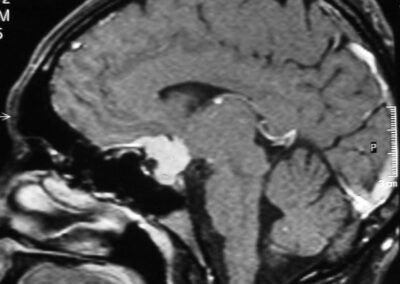

El diagnóstico se puede confirmar y el tumor localizar mediante:

• TAC cerebral

• RM cerebral

• Angiografía cerebral